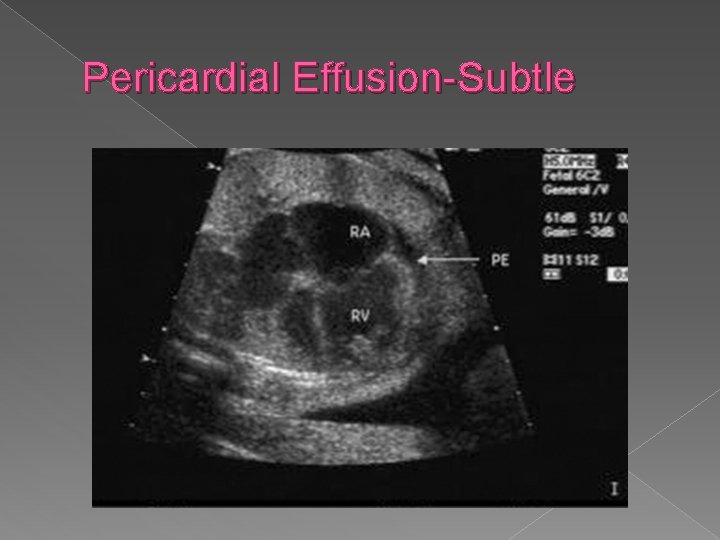

Pericardial effusion � “Fluid around the heart" is an abnormal accumulation of fluid in the pericardial cavity. Because of the limited amount of space in the pericardial cavity, fluid accumulation will lead to an increased intrapericardial pressure and this can negatively affect heart function. When there is a pericardial effusion with enough pressure to adversely affect heart function, this is called cardiac tamponade. Pericardial effusion usually results from a disturbed equilibrium between the production and re-absorption of pericardial fluid, or from a structural abnormality that allows fluid to enter the pericardial cavity.

Pericardial Effusion-Subtle